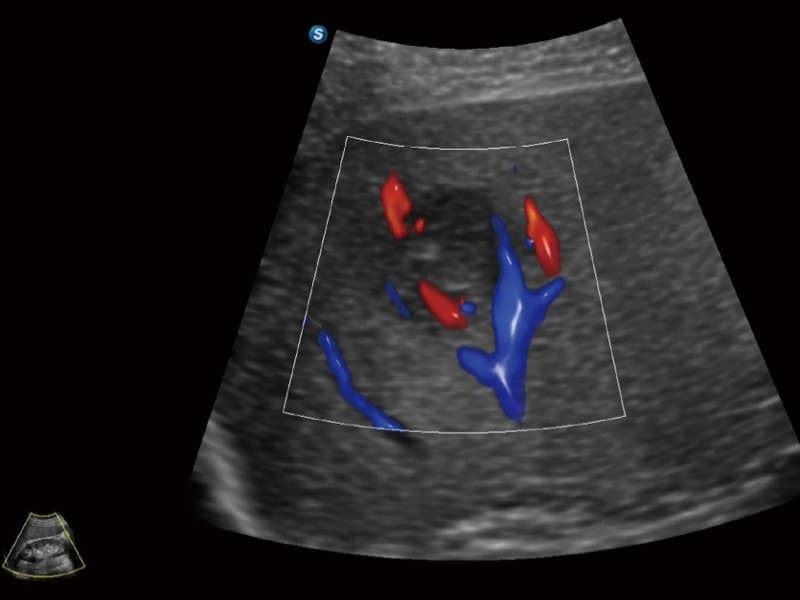

Klinische Bilder

- Radiologie: Quantitative Beurteilung der Lebersteatose durch ATI, Strain-Elastographie und kontrastverstärkter Ultraschall (CEUS)